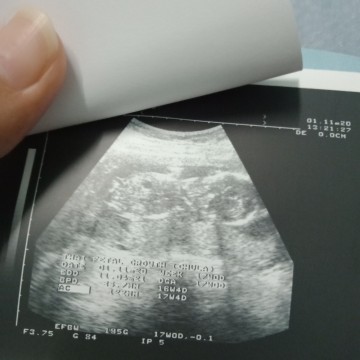

คุณหมอบอกว่าในใบซาวด์นี้เห้นเจี๊ยวน้องตรงวงกบมเล็กๆอะคะ แม่ว่าใช่ใมคะ 😅